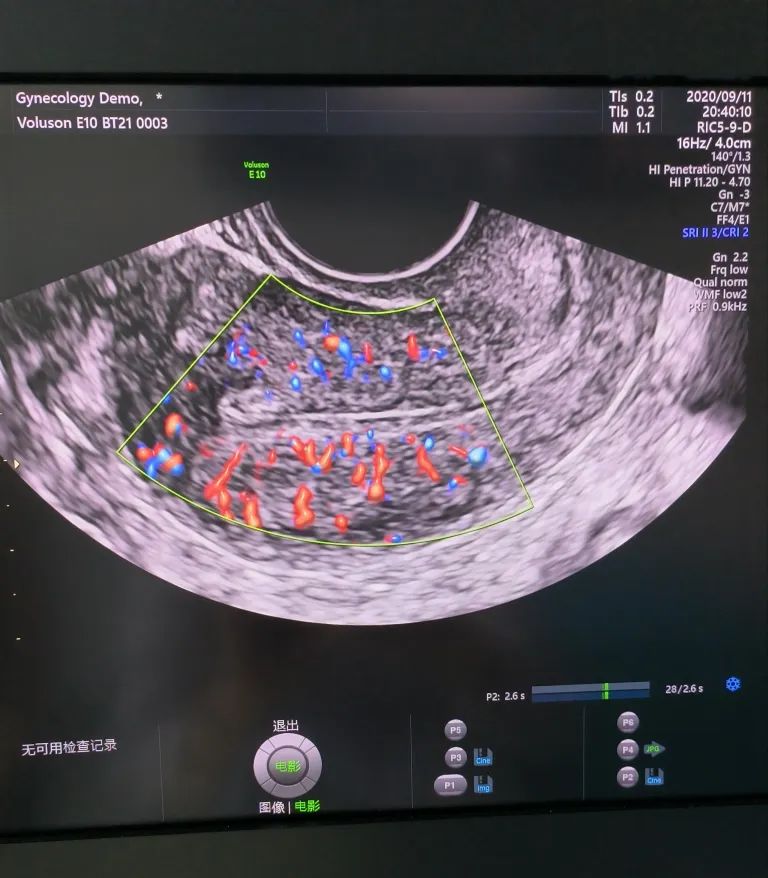

經(jīng)陰道超聲是在陰道超聲探頭上套上避孕套,將探頭伸入陰道進(jìn)行檢查。由于探頭位置接近子宮和卵巢,圖像更清晰,檢查結(jié)果更準(zhǔn)確。而且不需要憋尿,相對節(jié)省時間。所以現(xiàn)在大部分醫(yī)院對有性生活史的婦女更愿意開展經(jīng)陰道超聲檢查。